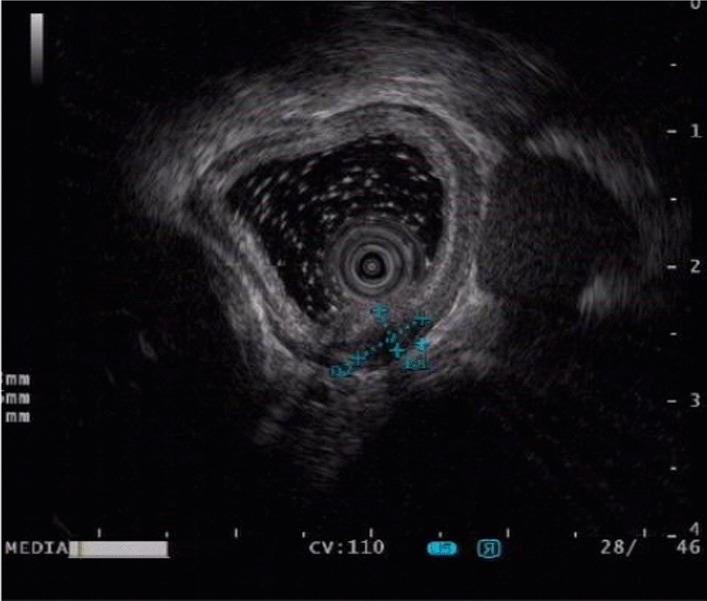

A 46-year-old male patient presented in 2018 with a submucosal tumor of the esophagus. Upon presentation, the tumor was approximately 10 mm in diameter, covered by normal mucosa, and located in the left posterior wall of the esophagus in a position that was 30 cm from the incisor. The tumor was discovered incidentally during gastroscopic examination. In March 2021, endoscopic re-examination revealed no significant changes in the tumor. Endoscopic ultrasound revealed an oval hypoechoic mass with a homogeneous internal echo that originated from the muscularis propria with a maximum cross section of 13 mm × 6 mm. Resection was performed under gastroscopy. The resection specimen was 12 mm × 5 mm in size and was a well-demarcated, elastic, hard, and tough with a gray section. Histologically, the specimen consisted of an abundance of smooth muscle fiber bundles intercalated among nerve fibers, but without malignancy. Immunohistochemical examinations revealed positivity for S-100 protein, caldesmon, NSE and desmin, but negativity for CD117, DOG-1, HMB45, and Melan A. There was also aberrant nuclear localization of beta-catenin. Collectively, these findings led to a diagnosis of esophageal NMC.

一名 46 岁男性患者于 2018 年因食管黏膜下肿瘤就诊。就诊时,肿瘤直径约 10mm,覆盖正常黏膜,位于食管左后壁,距门齿 30cm。肿瘤是在胃镜检查中偶然发现的。2021 年 3 月,内镜复查发现肿瘤无明显变化。内镜超声显示椭圆形低回声肿块,内部回声均匀,起源于固有肌层,最大横截面积为 13mm×6mm。在内镜下进行了切除。切除标本大小为 12mm×5mm,界限清楚,弹性硬韧,切面呈灰色。组织学上,标本由大量平滑肌纤维束穿插于神经纤维之间,但无恶性表现。免疫组织化学检查显示 S-100 蛋白、钙调蛋白、NSE 和结蛋白阳性,CD117、DOG-1、HMB45 和 Melan A 阴性,β-连环蛋白异常核定位。综合这些发现,诊断为食管 NMC。